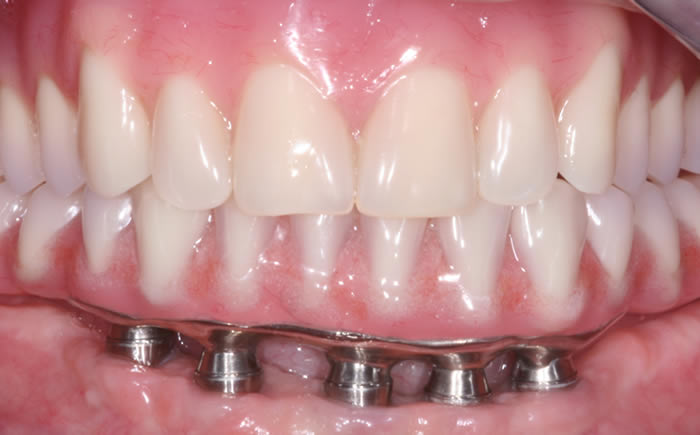

Full arches of teeth replaced by dental implants

Case One (5 images)

Full set of lower teeth fixed onto five dental implants.